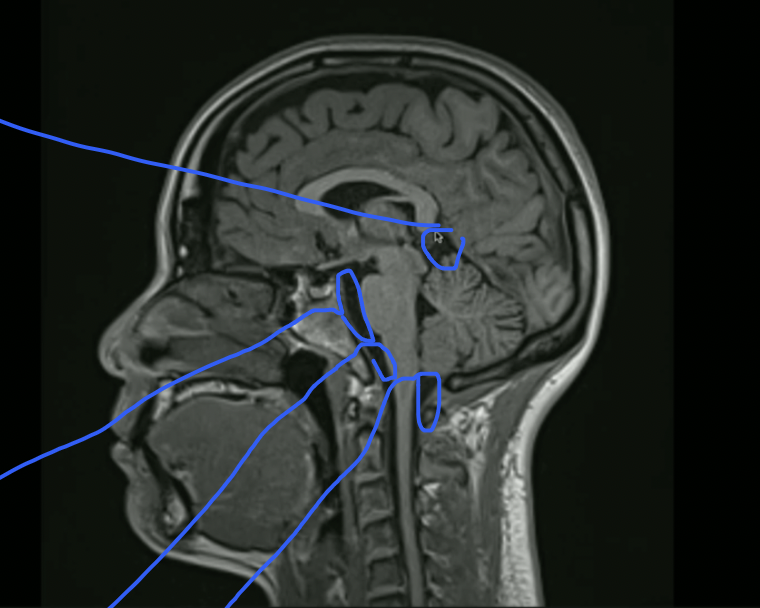

<p>What is Top + Bottom Circle + Arrow?</p>

What is Top + Bottom Circle + Arrow?

• Top: 3rd Ventricle

• Bottom: 4th Ventricle

• Arrow: Cerebral Aqueduct

<p>What Portion of the Corpus Callosum is this?</p>

What Portion of the Corpus Callosum is this?

• Genu